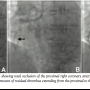

the proximal right coronary artery (RCA) (Figure 1A). Percutaneous coronary intervention (PCI) was performed via the right transradial artery using a 6 Fr Ikari-Curve Right guide catheter (IR-1.0, HeartRail II, Terumo Corporation). After crossing the lesion with a guidewire (Neo’s Rinato, Asahi Intecc, Co., Ltd.), thrombectomy was attempted several times using an aspiration catheter (TVAC-S6; Nipro Corporation) (Figure 1B). However, a significant amount of thrombus remained, extending from the proximal to mid segment of RCA (Figure 1C). The 6 Fr Ikari-Curve Right guide catheter was inserted deep into the distal RCA for manual thrombus aspiration. A 30-cc syringe was attached to the Y-connector, maintaining constant negative suction, and the guide catheter was slowly withdrawn from the distal to proximal RCA while the guidewire remained in RCA to maintain access to the distal vasculature of the occluded

artery (Figure 2A). We aspirated several times to ensure there was no aspirate left in the guide catheter. This procedure led to successful retrieval of a large, cylindrical, red–white thrombus (Figure 2B). Angiography revealed a significantly improved RCA appearance with no residual thrombus or distal embolization (Figure 2C). It also showed ulceration of the proximal RCA (Figure 3A). Based on the angiographic appearance, this ulceration was considered the culprit (plaque rupture) site. Therefore, a 3.5 mm × 23 mm coronary stent (S-Stent™; Biosensors International Group, Ltd.) was deployed into the proximal RCA. An excellent final angiographic result with no distal embolization was achieved (Figure 3B).